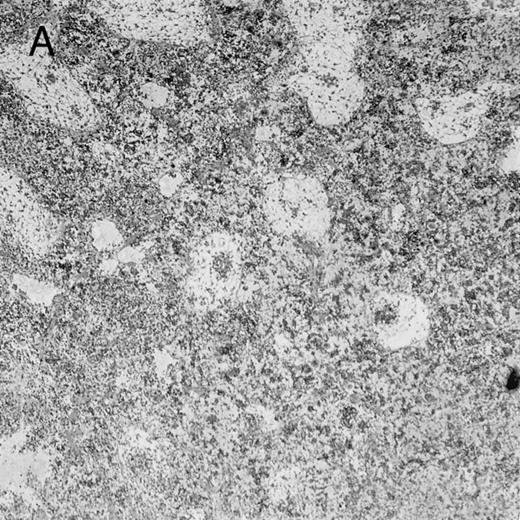

Histologic findings. Organs were collected at different times after BMT and tissue sections were stained with hematoxylin and eosin. Original magnifications for spleen (left) and liver (right) are ×40 and ×100, respectively. (A) B6 mice receiving FVB BM plus EpTK T cells. (B) Control group receiving BM only.

(C) B6 mice receiving FVB BM plus EpΔTK T cells and treated with GCV. (D) B6 mice receiving FVB BM plus EpΔTK T cells, treated with GCV, and developing a late onset GVHD (day 54).

FVB BM-grafted B6 mice: a model of lethal GVHD.We developed a model of GVHD resulting in 100% mortality soon after BMT using FVB mice, a strain not previously used as BM donors in experimental allogeneic BMT. We tested different combinations of recipient irradiation doses, as well as injected BM cell and CD3+ peripheral T-cell numbers. When 10-Gy–irradiated B6 mice were reconstituted with 107 FVB BM cells, we observed prolonged survival, whereas all ungrafted animals died before day 16 (Fig 2). In these conditions, more than 98% of splenocytes were of donor origin (Fig 3A). When 107 CD3+ peripheral T cells from mice of FVB genetic background were added to the FVB BMT, all animals died of GVHD between days 7 and 34 (Fig 2). Similar results were obtained using either PBS-treated mice receiving EpTK or EpΔTK peripheral T cells or GCV-treated mice receiving FVB nontransgenic peripheral T cells. Notably, this observation also indicates that both TK- and ΔTK-expressing T cells in the absence of GCV are fully competent to induce a lethal GVHD. Histopathologic examination of spleen and liver of these animals showed characteristic GVHD lesions such as (1) architecture disruption, necrosis, and congestion in the spleen; (2) hepatic periportal necrosis; (3) mononuclear portal infiltrates; and (4) endothelialitis of portal or centrolobular veinules (Fig 4A). By comparison, B6 mice receiving only FVB BM had a normal histology (Fig 4B).

Using this delivery mode, we observed that mice receiving a 7-day GCV treatment initiated at the time of transplantation were protected from GVHD. At day 60, the survival rate was 100% in the GCV-treated group receiving EpTK CD3+ T cells, and was still 92% at the end of a 120 day follow-up (Fig 2A). Protected mice were apparently healthy, presented no visible skin lesions, and gained weight comparably to controls receiving only BM (data not shown). Hematologic reconstitution was analyzed by flow cytometry at different times from day 14 to day 212. Splenocytes of GCV-treated animals were of donor H-2q origin in the B-cell (B220+) and non–B-cell (B220−) compartments, the latter containing donor Thy1.1+ T cells but no recipient Thy1.2+ T cells (Fig 3B). Finally, histological analysis in these animals showed nodular architecture in the spleen and no significant hepatocyte necrosis or portal mononuclear cell infiltrates in the liver (not shown) and similar to control animals receiving only BM. Taken together, these data indicate that a GCV treatment, administered at the onset of allogeneic BMT and with a course as short as 7 days, abrogates GVHD and allows a full recovery from the lethal irradiation.

Protection from GVHD was slightly less efficient in the group receiving EpΔTK CD3+ T cells. The survival rate was 79% at day 60 and 67% at day 120 (Fig 2B). However, two different outcomes must be distinguished. On the one hand, a majority of mice behaved as GCV-treated animals receiving EpTK T cells. They were apparently healthy, presented no skin lesions during a 120-day observation period, and showed complete donor-type hematologic reconstitution. There were no histological signs of GVHD in the spleen or liver (Fig 4C).

On the other hand, 5 of 19 mice exhibited signs suggesting the occurrence of a delayed GVHD (Table 1). Clinically, these animals presented weight loss and/or skin lesions on ears, neck, limbs, or abdomen, but only after day 40. In the absence of any further GCV treatment, 2 mice died 14 and 29 days after the occurrence of these signs (Table 1A) with histological signs of severe GVHD (Fig 4D). These results suggest that, in these mice, the 7-day GCV treatment was sufficient to prevent early, but not delayed GVHD.